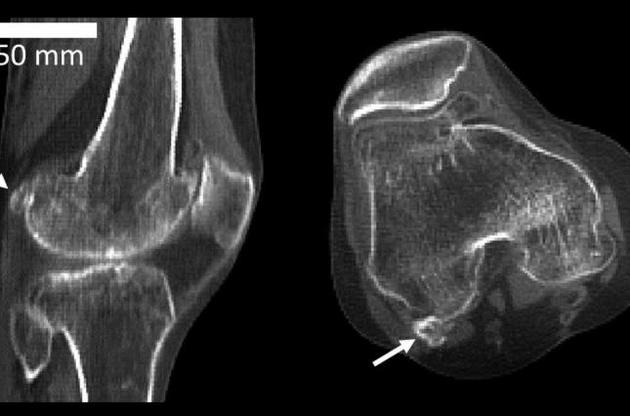

По словам ученых, фабелла может уменьшать трение в сухожилиях, перенаправив мышечные силы, или, как в случае с коленной чашечкой, увеличить механическую силу мышцы. Вместе с тем, у наличия фабеллы есть и недостатки: люди, страдающие от остеоартрита коленного сустава обладают в вдвое большей вероятностью иметь фабеллу, чем люди без заболевания. Кроме того, эта кость может вызвать боль и дискомфорт, а также мешать операциям по замене коленного сустава.

"Нас учат, что человеческий скелет содержит 206 костей, но наше исследование ставит это под сомнение. Фабелла - кость, которая не имеет видимой функции и вызывает у некоторых боль и дискомфорт, также может потребовать удаления, если она вызывает проблемы. Возможно, скоро фабелла будет известна как "аппендицит скелета". По мере того как мы эволюционировали, мы, похоже, утратили потребность в фабелле. Теперь она просто вызывает проблемы. Интересный вопрос в том, почему она проявляется вновь именно сейчас", - заявил ведущий автор исследования Майкл Бертом.